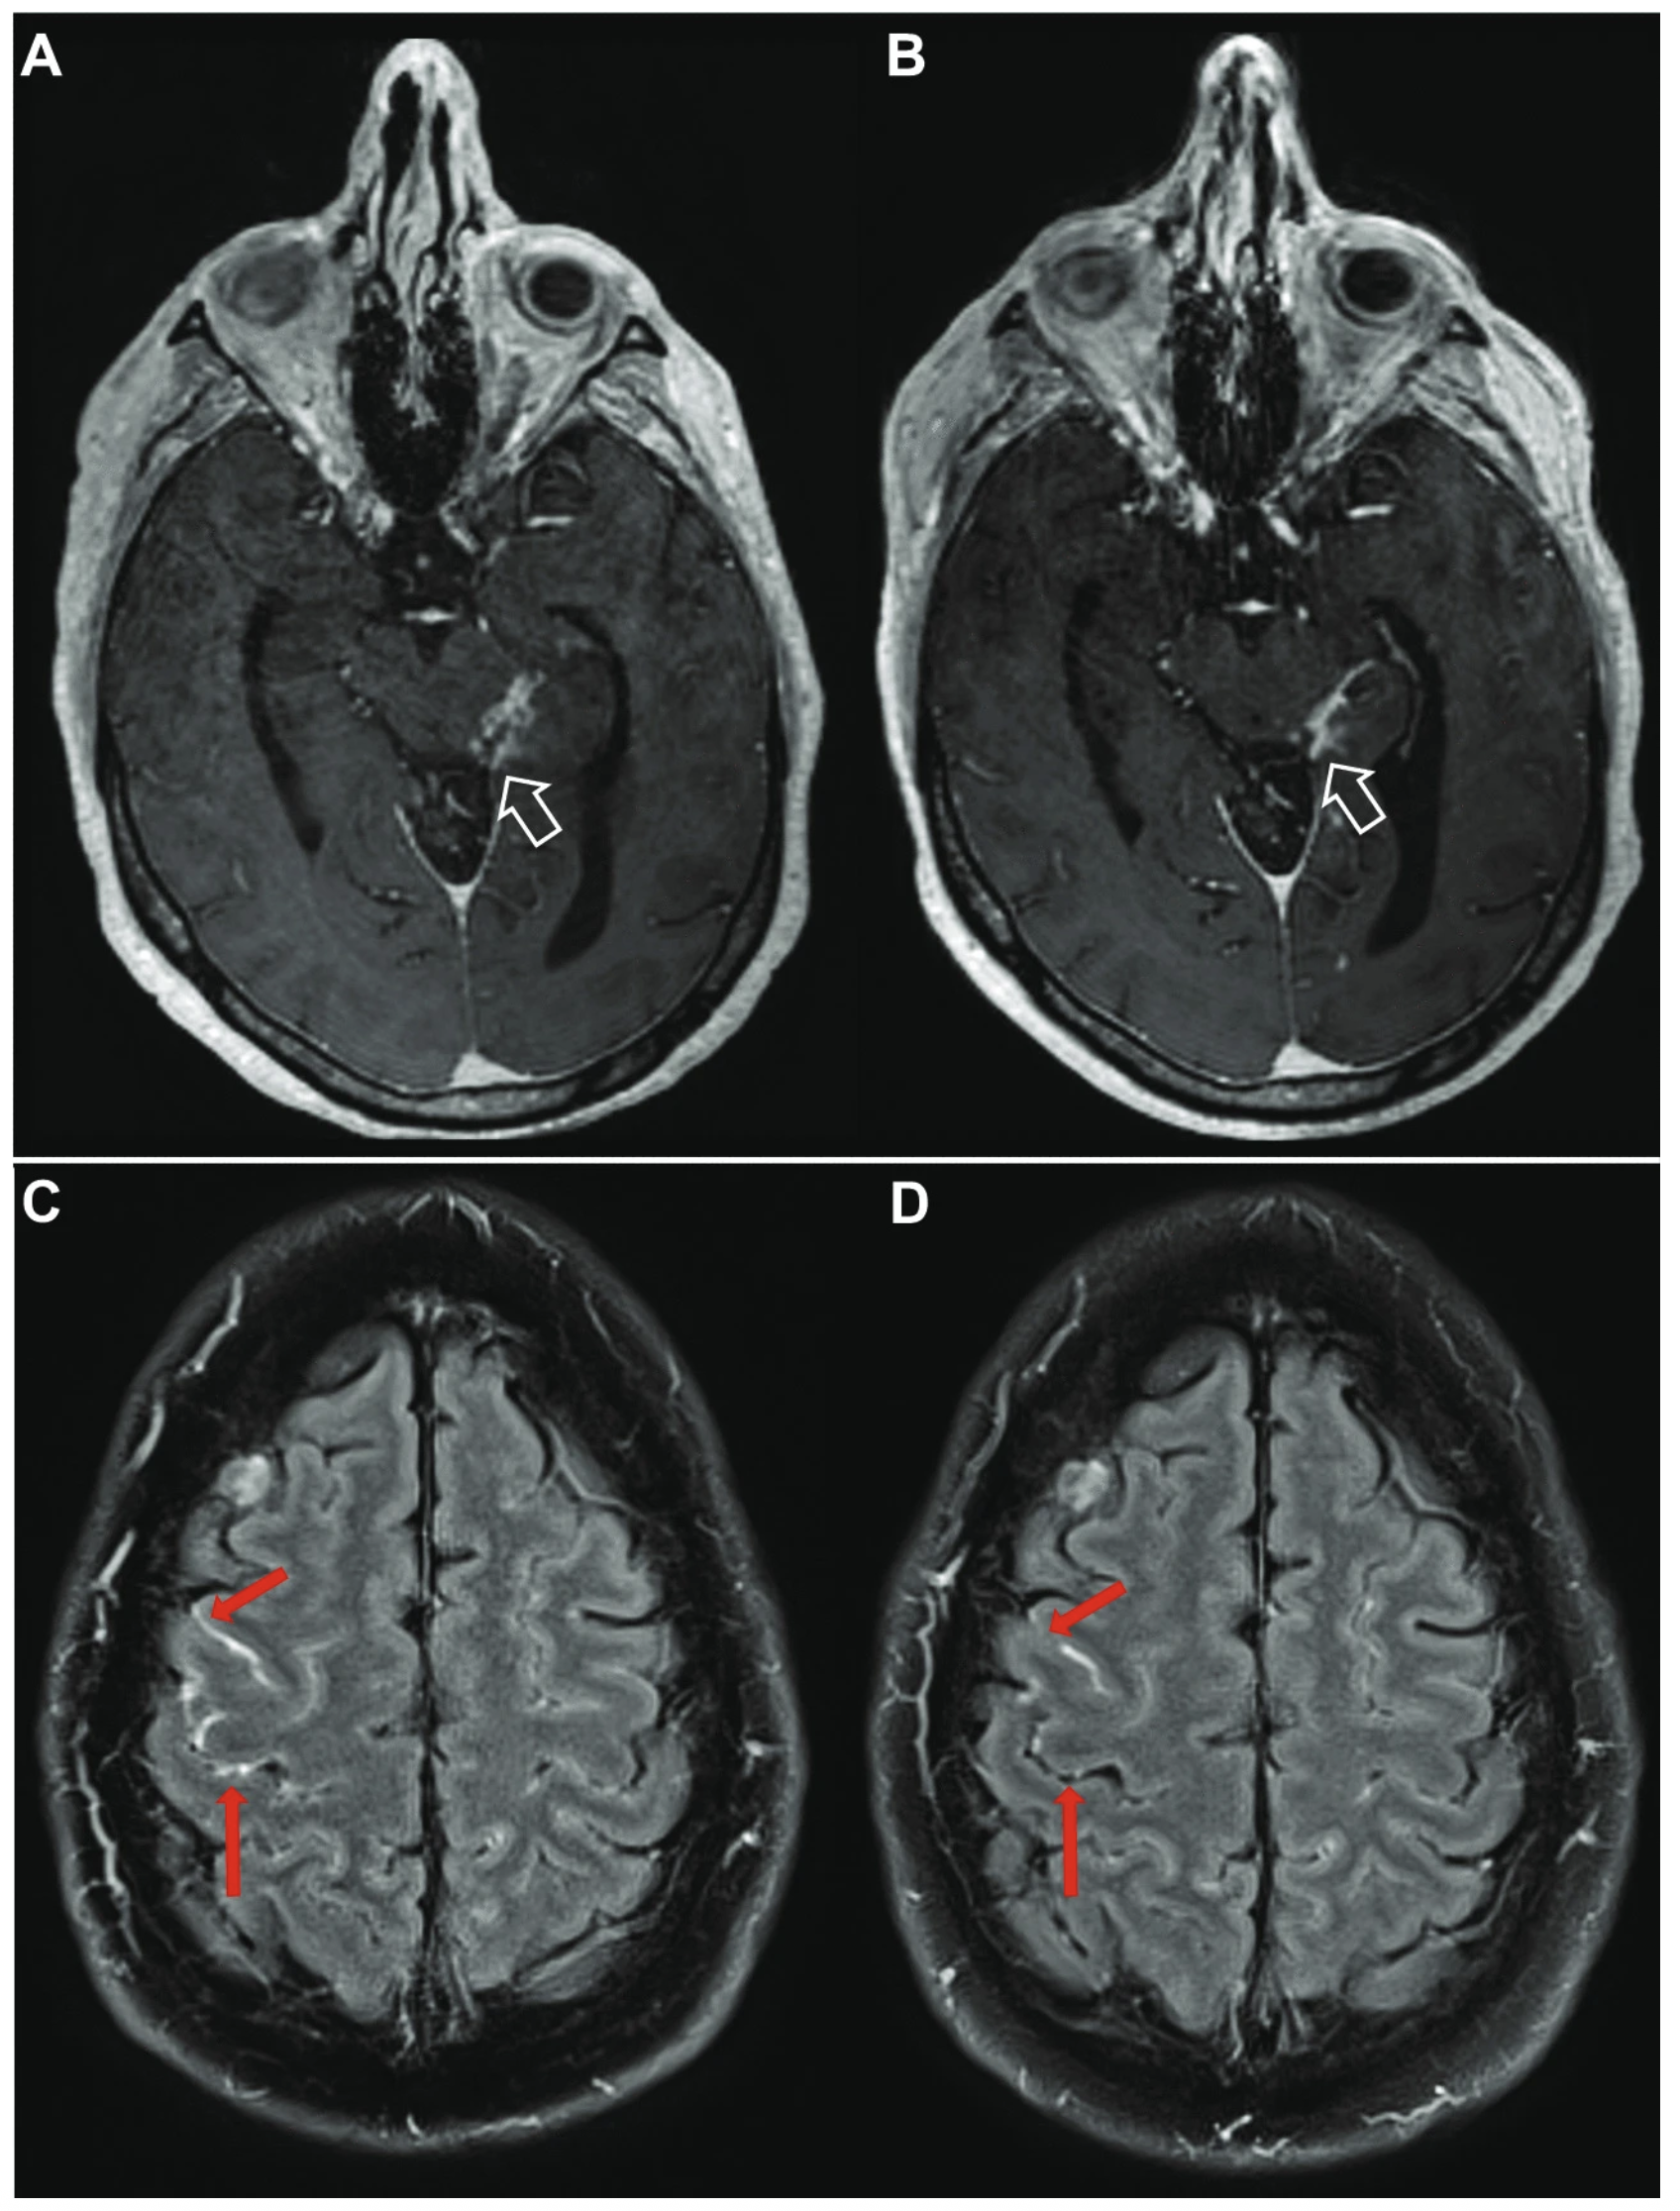

Persistent neurological symptoms and elevated intracranial pressures in a previously healthy host with cryptococcal meningitis.

El-Atoum M, Hargarten JC, Park YD, Ssebambulidde K, Ding L, Chittiboina P, Hammoud DA, Anjum SH, Glassman SR, Merchant S, Williamson PR, Hu JC. BMC Infectious Diseases. 2023. 23(1):407. doi: 10.1186/s12879-023-08349-y. PMID: 37316806; PMCID: PMC10265895.